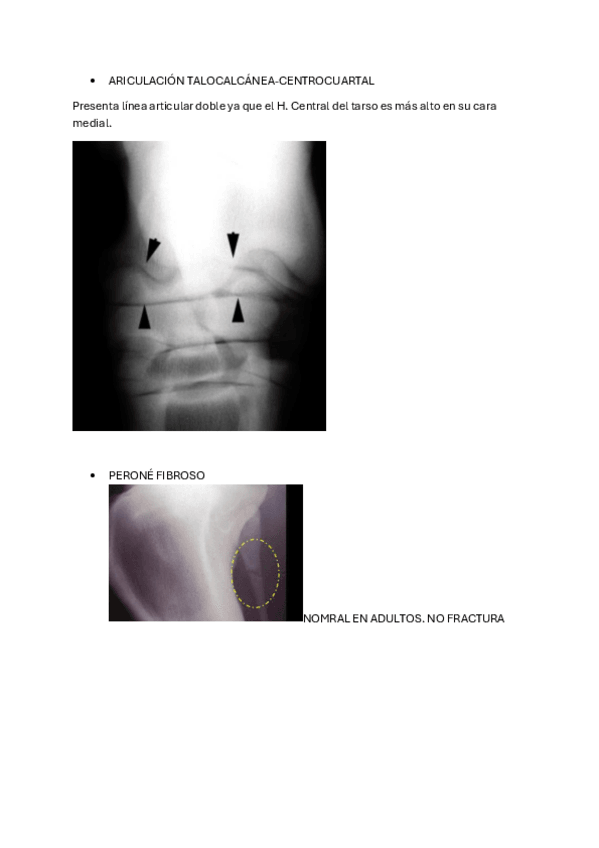

MP EQUINO

He publicado nuevos apuntes de 3º Diagnóstico Por la Imagen: MP EQUINO

Apunte-extra.pdf

Patologias.pdf

Proyecciones.pdf